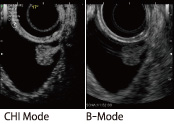

超音波造影剤から反射された超音波高調波信号を選択的に表示し、受信信号強度を増強し画像化するモードです。